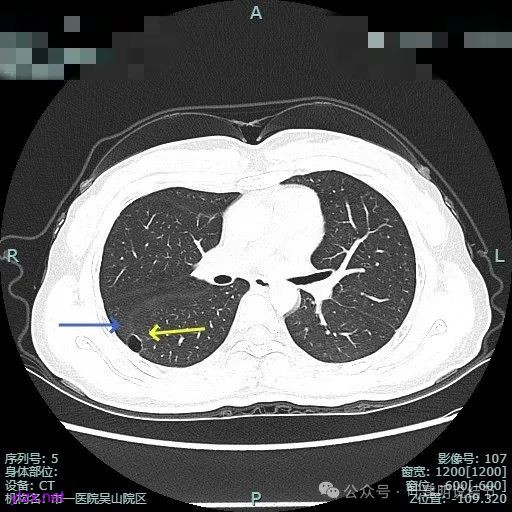

薄层上看病灶贴着叶间裂与胸膜,此层囊壁薄,囊腔明显。

囊壁局部有增厚。